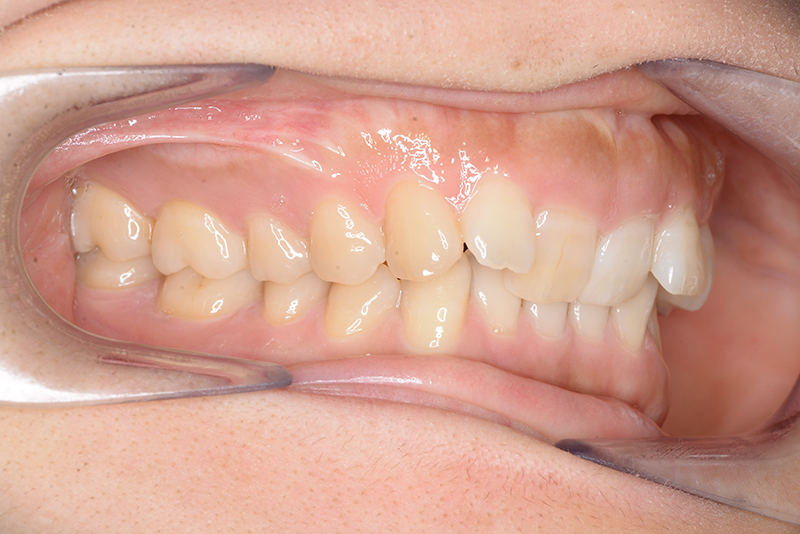

口腔内所見 大臼歯、犬歯関係はⅡ級で、上顎中切歯は舌側傾斜しており、over jet1.5mm,over bite 6.0mmいわゆるⅡ級2類であった。

批評・予后 上顎臼歯は軽度に近心傾斜しつつ、歯列遠心部には奥行きがあり、下顎歯列には叢生は認められず、スピー湾曲も軽度であること。また軟組織上の問題もないため、上顎歯列の遠心移動による治療が妥当だと判断した。治療後において上顎歯列の遠心傾斜と共に下顎はカウンタークロックワイズローテーションをしながら咬合の緊密化が得られた。